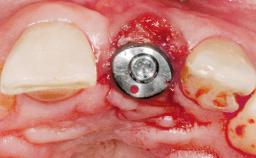

A 30-year-old female patient had lost tooth 21 and was referred to our clinic for consultation and treatment. Due to advanced apical infection, tooth 21 had been extracted two months earlier at another clinic and an acrylic-resin tooth had been bonded to the adjacent teeth. The patient desired implant treatment to avoid any damage to the adjacent natural teeth. While the patient had no history of any systemic disorder, she was a heavy smoker and exhibited medium to advanced periodontitis in the entire jaw. After the initial treatment to achieve a pocket probing depth of less than 4 mm and no bleeding on probing, a decrease in the height of the papillae mesial and distal to the extraction site and overall gingival recession were observed.

Type of Implants One-Piece|Reduced-Diameter

Bone Augmentation Horizontal|Staged

Augmentation Materials Autogenous chips|Membrane